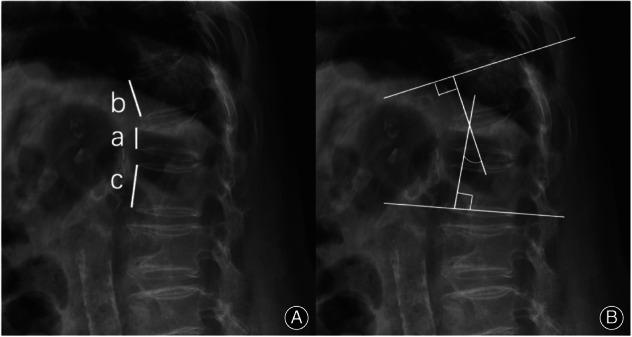

This prospective analysis evaluated 74 patients with stage I and II Kümmell's disease who underwent PVP treatment at our hospital from December 2019 to December 2021. The participants were divided randomly into groups based on whether the bone cement-gelatine sponge composite was used during the surgery. The two groups were the bone cement-gelatine sponge composite group (GS group, comprising 37 patients) and the no bone cement-gelatine sponge composite group (N-GS group, comprising 37 patients). The independent samples t-test and chi-square test were employed to compare general information, operative time, cement injection volume, intraoperative bleeding, and bone cement leakage between the two groups. Additionally, the visual analogue scale (VAS) score, Oswestry disability index (ODI), anterior vertebral height ratio (AVHR), and the kyphotic Cobb angle were compared between the two groups at the preoperative, 2 days postoperative, and 6 months postoperative stages using repeated measures analysis of variance.

All patients were followed up for more than 6 months, with an average of (11.19 ± 2.21) months. No significant differences were observed in terms of the operative time, cement injection volume, and intraoperative bleeding between the two groups (P > 0.05). The incidence of bone cement leakage in the N-GS group (32.43%) was significantly higher than that in the GS group (5.41%), and the difference was statistically significant (P < 0.05). The VAS score and ODI of the two groups at postoperative 2 days and 6 months improved significantly (P < 0.05). The AVHR and kyphotic Cobb angle were corrected to a certain extent (P < 0.05); however, no significant difference was observed between the two groups (P > 0.05).